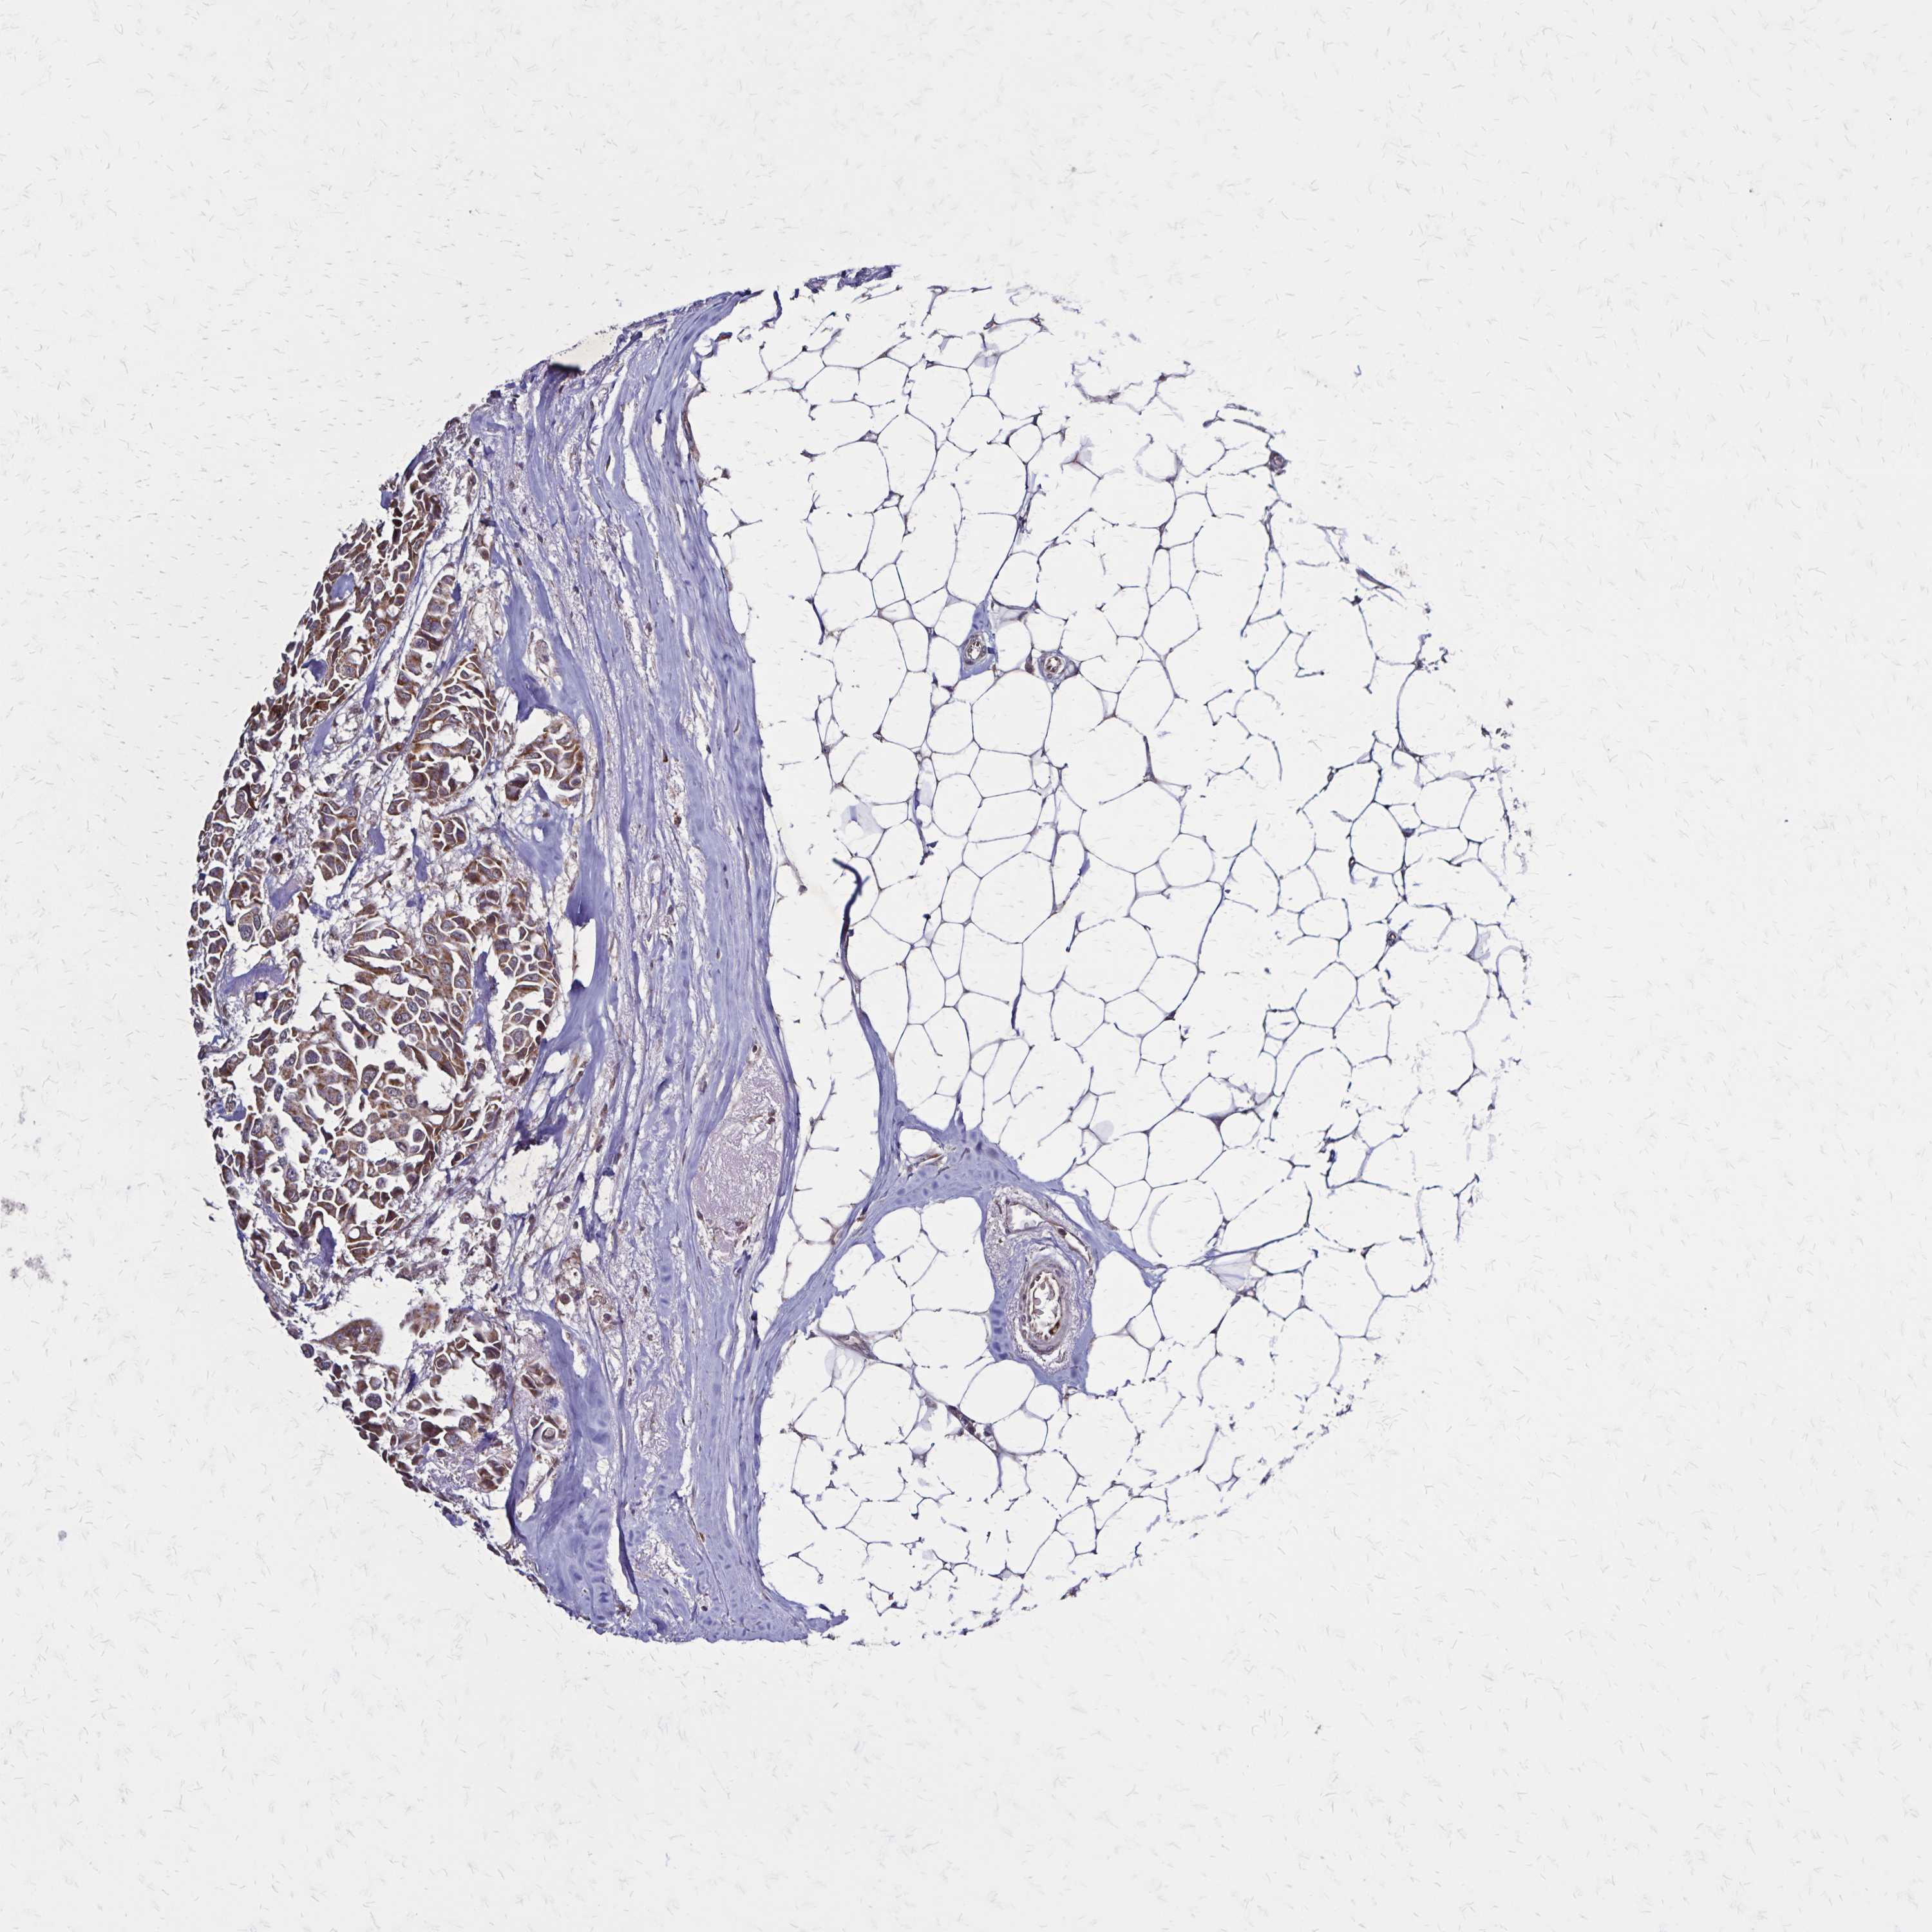

CANCER BREAST CANCER Show tissue menu

BRCA TCGA BRCA VALIDATION PROTEIN EXPRESSION

ANTIBODIES

AND

VALIDATION